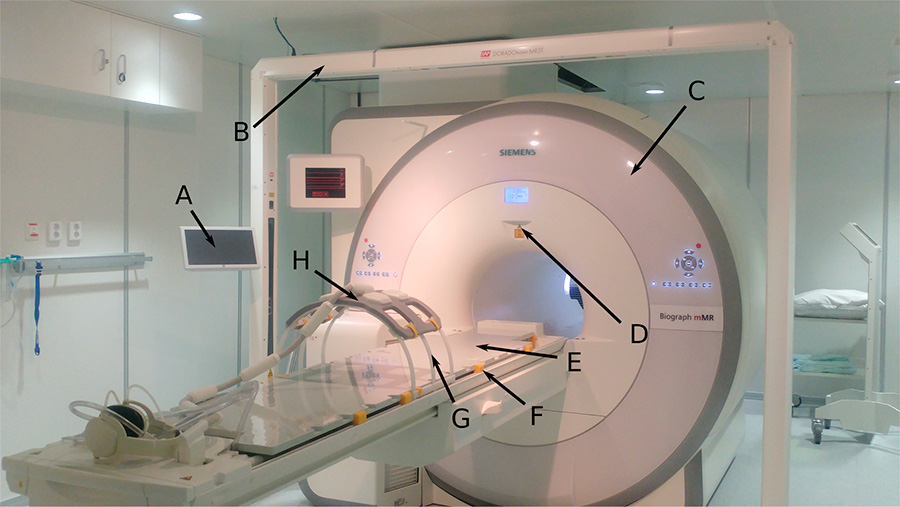

During the last years, the use of MR imaging in radiotherapy planning has increased rapidly due to its superior soft tissue contrast. MR images allow a more accurate delineation of the tumour and organs at risk, compared to CT which traditionally has been considered as the primary modality in radiotherapy. As the linear accelerator has a flat table, MR scanners used in radiotherapy also needs to have flat table overlay to be able to image the patient in treatment position. The scanner should also have a bore large enough to make room for the radiotherapy specific equipment, such as immobilization devices and coil bridges.

The coil bridges are used to create a gap between the patient and the receiver coil to avoid deformation of the patient. But still the gap should be minimal since the signal decreases with increasing distance. The addition of an external laser bridge is needed to position the patient as precisely as possible. The voxel intensity of CT images provides direct information about the electron density of the tissue, providing information about how photons will interact with the tissue. This data is needed to accurately calculate the resulting radiation dose.

The PET/MR scanner at St. Olavs hospital (Siemens Biograph mMR) with equipment needed for MR-based radiotherapy. A) Tablet to control the laser bridge, B) laser bridge, C) the magnet, D) scanner isocenter-location laser, E) Mediboard flat table overlay, F) blocks used to secure the flat overlay on top of the standard curved patient table, G) torso coil holder, H) MR receiver coil placed on the coil holder.